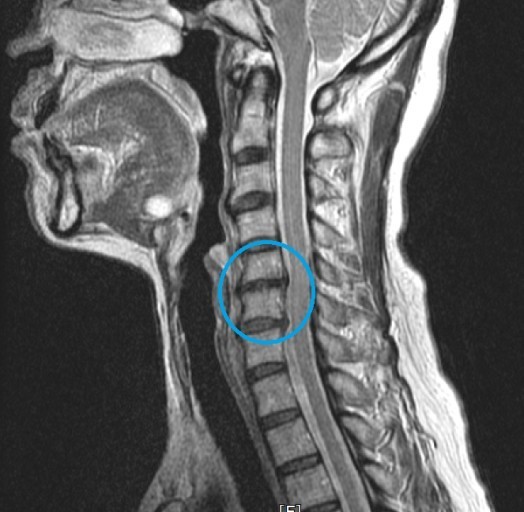

오늘은 목 건강을 위협하는 질환, **목디스크(경추 추간판 탈출증)**의 증상에 대해 이야기하려 합니다. 목디스크는 목뼈 사이에 있는 디스크가 제자리를 벗어나 신경을 압박하면서 발생하는 질환입니다.

- 설명: 목디스크가 심하게 진행되어 척수를 압박하면 하체까지 증상이 나타날 수 있습니다. 다리에 힘이 빠지고, 보행이 불안정해지며, 심한 경우 마비 증상이 나타나기도 합니다. 이는 즉시 치료가 필요한 심각한 합병증입니다.